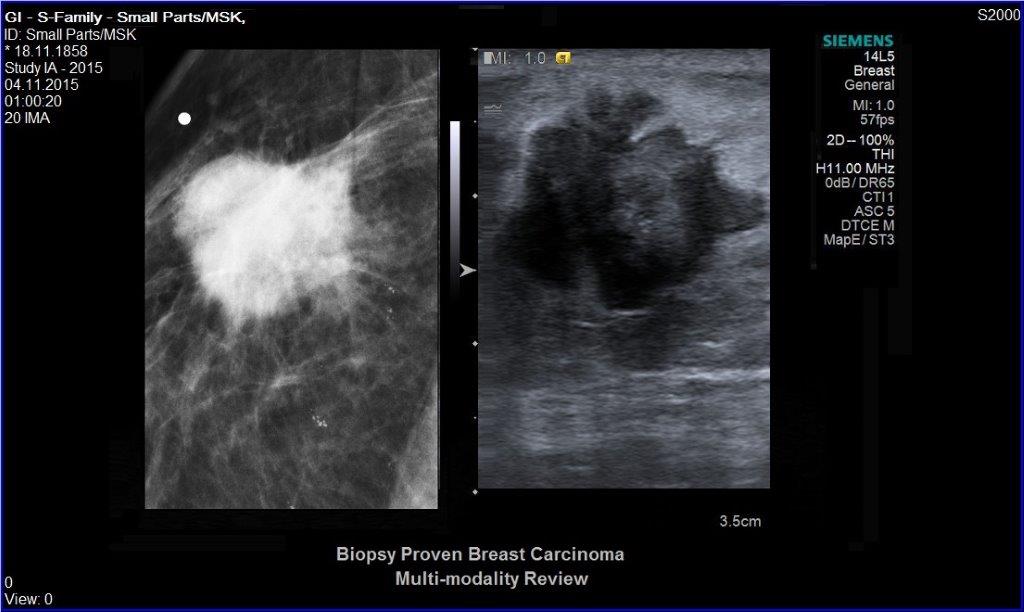

• Ultraschalluntersuchung der Brust

• Biopsien unter Ultraschall